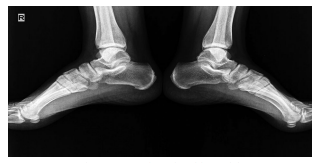

Dose reduction was used in patients with moderate and severe back pain, constituting 37.2% of the patients describing the complaint. The vast majority of these patients responded to dose reduction, while eight (10.2%) patients needed to use non-steroidal anti-inflammatory drugs for pain relief. Sacroiliitis was present in four (4%) patients, including three females and one male. There was no statistically significant difference between the sexes for sacroiliitis development (p=0.25). Bilateral sacroiliitis was detected in one patient (Figure 1). Sacroiliitis regressed 1.5 to 2.5 months after isotretinoin treatment cessation in all patients. The patients diagnosed with sacroiliitis were followed for six months. Three (3%) patients described myalgia, which was of mild severity and did not require additional treatment. Among these patients, two female patients also described low back pain. Creatine kinase (CK) elevation was observed in 18 (18.1%) patients, including 13 males and two females, one to three months after the beginning of treatment (p=0.1). The elevated CK values ranged between 233 and 940 IU and returned to normal levels after dose reduction. One (1%) female patients who was on low-dose isotretinoin treatment (0.5 mg/kg) was diagnosed with enthesitis at three months of treatment (Figure 2).